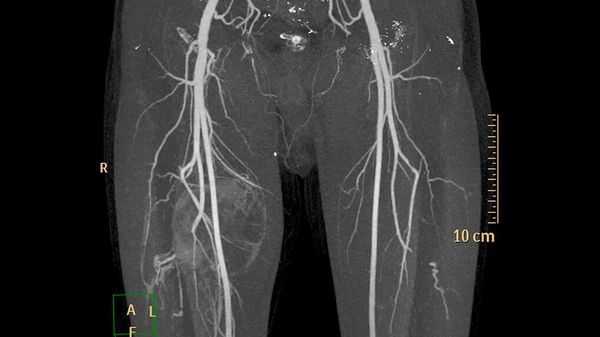

- Эмболизация - проводится перед хирургической операцией, для профилактики кровоизлияний. Через тазобедренный прокол внедряется тонкий катетер, направляется к сосудам, которые снабжают ГМ кровью и подводится к самой патологии. Через трубку подается эмболизирующий материал и блокирует пораженные места сосудов и останавливает подачу кровотока.

Микрохирургическое удаление мальформации - в этом случае выполняется трепанация черепа, с последующем иссечением мальформации. Является самым радикальным, но не самым безопасным методом, особенно для больших или гигантских, а также располагающихся в функционально значимых зонах мальформаций. Эндоваскулярная эмболизация мальформации - выполняются путем прокола артерии, чаще бедренной (в паховой области), с последующим заведением специальных катетеров в тело артериовенозной мальформации и заклеивания ее изнутри с помощью специальных клеевых композиций. Лечение может быть как одномоментным, если мальформация небольшого размера, так и многоэтапными растягиваться на несколько лет. Количество этапов зависит от размера мальформации, ее строения, особенностей ранее проведенных операций. За одну этап стараются выключать около 30% объема мальформации, хотя понятие процента эмболизации носит условный и субъективный характер. При этом метод эффективен в 80-90% для маленьких, 40-50% для средних и только в 10-30% для больших или гигантских мальформаций. Комбинированное лечение - возможно сочетание первых двух методов. В этом случае проводится эндоваскулярная эмболизация (на сколько это возможно технически и безопасно) с последующим ее микрохирургическим удалением. Лучевая терапия - возможно облучение на аппаратах гамма-нож, линейном ускорителе, протонном пучке. Как правило, это касается мальформаций размер которых не превышает 3 см и при условии отсутствия высокоскоростных артериовенозных шунтов в ее теле. Эффективность метода оценивается не сразу, а в течение 2-3 лет с момента облучения. В последующем выполняют контрольную ангиографию, по результатам которой и принимают решение о дальнейшей тактики лечения.